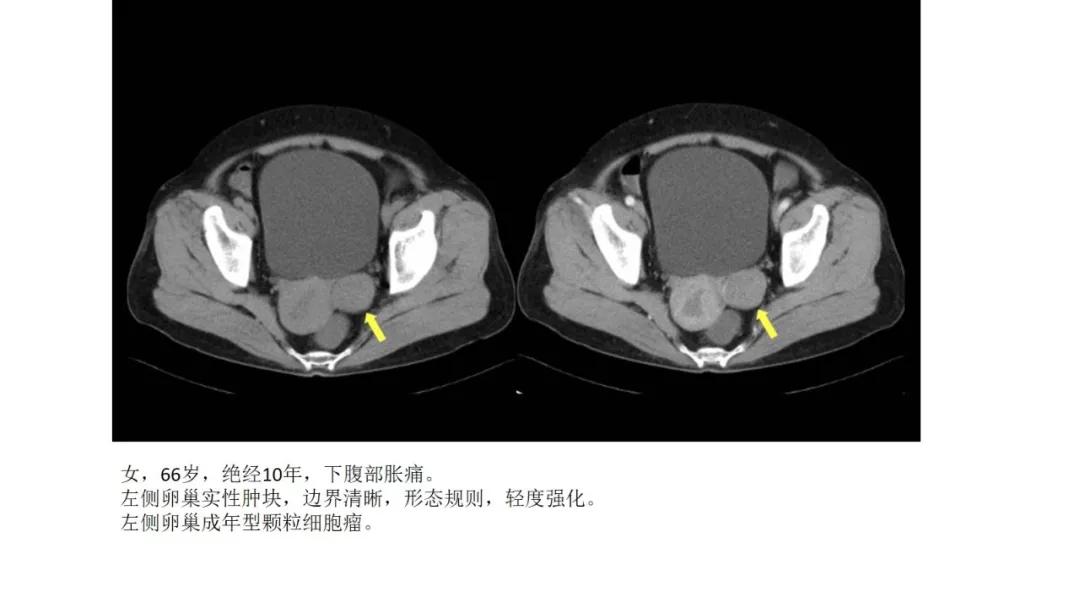

性索间质性肿瘤:较少见,良性多,多数肿瘤具有内分泌功能,可伴有内分泌症状及子宫内膜增生,内膜癌,乳腺疾病。多呈囊实性及实性肿块,界清,形态规则或欠规则,少有壁结节,多数呈实性伴有大片变性低密度改变,轻中度强化。

高雌激素症状:颗粒细胞瘤、卵泡膜细胞瘤(绝经期后出血及阴道不规则出血、性早熟、子宫内膜增生、乳房胀痛)

- 颗粒细胞瘤与交界性浆液性囊腺瘤虽然恶性程度都不高,但均可在切除多年后复发,因此术后需要及时随访复查,类似的还有透明细胞癌。